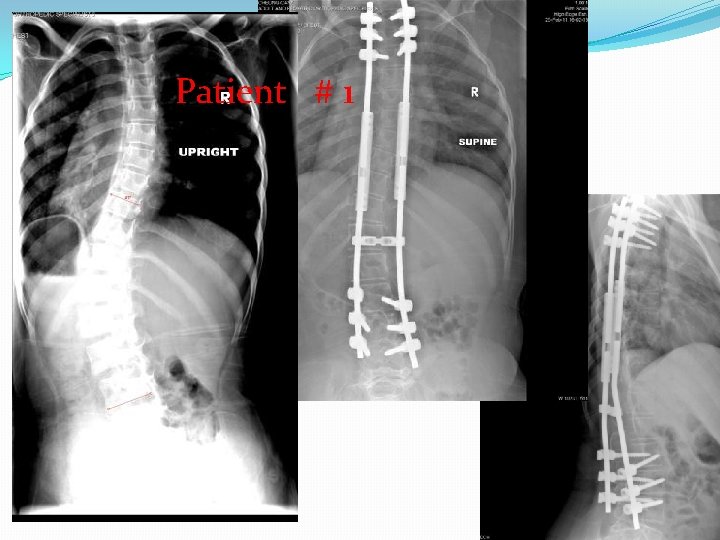

�At the time of surgery, two of these children were over 12 years of age and underwent posterior spinal arthrodesis with segmental spinal instrumentation from T 2 to pelvis. The other patients were under 10 years of age and were treated with spinal instrumentation in a growing rod construct, without arthrodesis. There were no complications from surgery with excellent sagittal and coronal correction of deformity obtained and maintained.

patient age at diagnosis (months) Age at Followsurgery up (months) months surgery Cobb pre-op Cobb post-op sagittal complica tions � #1 96 125 54 ** 54° 18° normal none � #2 96 148 25 *** 66° 53° normal none � #3 96 * 64° � #4 72 117 14 ** 42° 8° normal none � #5 24 154 14 *** 64° 4° normal none * normal • * Pending surgery • ** Segmental spinal instrumentation without arthrodesis • *** Segmental spinal instrumentation with arthrodesis

Patient # 1